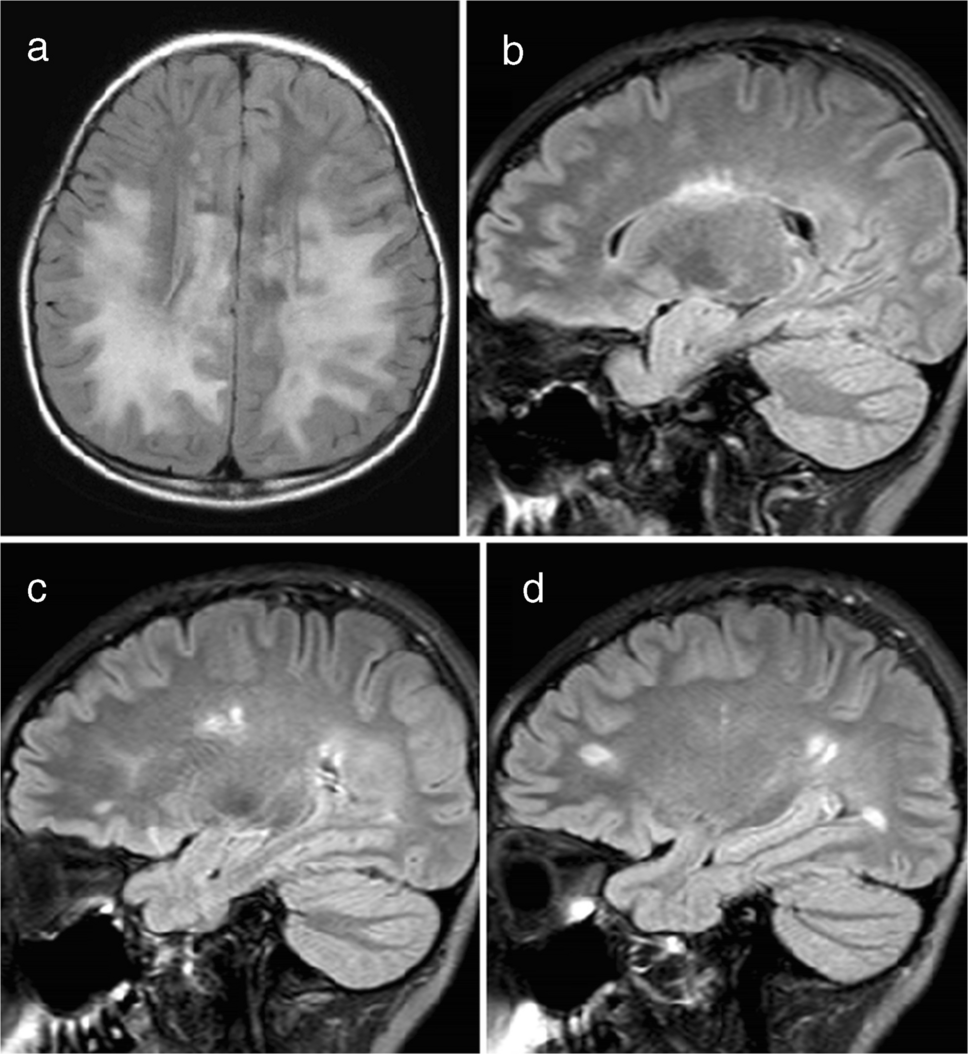

A cortical encephalitis pattern was identified in three patients, and an aseptic meningitis pattern was seen in six patients (Figs. 4 and 5, respectively). Tumefactive demyelinating lesions were observed in three cases. These lesions were large (> 2 cm) and unifocal, resembling either neoplastic processes or localized abscesses (Fig. 6). The lesions were located in the periventricular white matter, thalamus, and subcortical white matter/cortex, respectively. Unlike typical tumors, these lesions did not demonstrate mass effect. A cerebellitis/brainstem encephalitis pattern was found in two patients (Fig. 7). One patient exhibited non-enhancing lesions in the cerebellar white matter and midbrain, while the other had poorly defined cerebellar cortical lesions with curvilinear enhancement. Among the miscellaneous patterns, one patient showed a leukodystrophy-like presentation (Fig. 8a), and another exhibited an MS-like pattern (Fig. 8b–d).

Fig. 4

Magnetic resonance images illustrate myelin oligodendrocyte glycoprotein antibody-associated diseases with a cortical encephalitis pattern. a Axial fluid-attenuated inversion recovery image from an 11-year-old girl with seizures and drowsiness shows gyral swelling in the left temporal lobe (arrows), with no associated white matter lesion. b, c Axial fluid-attenuated inversion recovery (b) and diffusion-weighted (c) images from another 11-year-old girl. There is subtle hyperintensity in the right medial parietal cortex (arrow in b), with a diffusion-restrictive lesion in the same region (arrow in c). The lesion was initially misinterpreted as cortical infarction

Fig. 5

Magnetic resonance images illustrate a myelin oligodendrocyte glycoprotein antibody-associated disease with an aseptic meningitis pattern in a 3-year-old girl with seizure. a, b Post-contrast axial T1-weighted images obtained at the midbrain level (a) and at the foramina of Monro level (b) reveal localized leptomeningeal enhancement in the right occipito-temporal region. c Axial T2-weighted image at the same level as (a) shows no significant abnormalities in the brain parenchyma